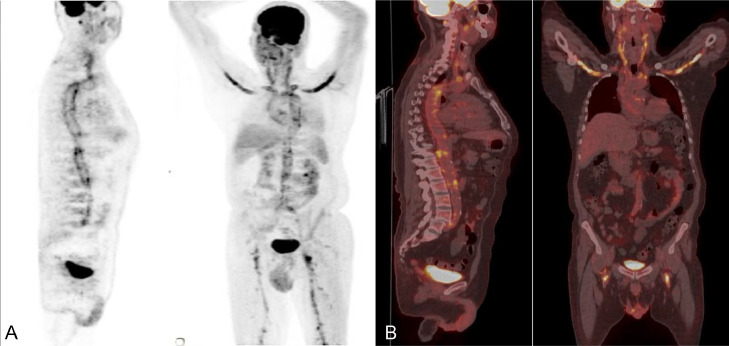

Furthermore, an 18F-FDG PET-CT was performed to delineate the full burden of the disease and revealed avid tracer uptake of the arch of the aorta and its major branches with involvement of the axillary and femoral vessels (Fig. 2).

Fig. 2.

(A) FDG-PET images in AP and lateral views showing tracer uptake in the arch of the aorta and its major branches with avid SUV max 7 uptake seen involving the subclavian, axillary and proximal femoral arteries bilaterally. (B)18F-FDG PET-CT in coronal and sagittal views showing avid tracer uptake in the arch of the aorta and its major branches extending to the axillary and femoral arteries bilaterally